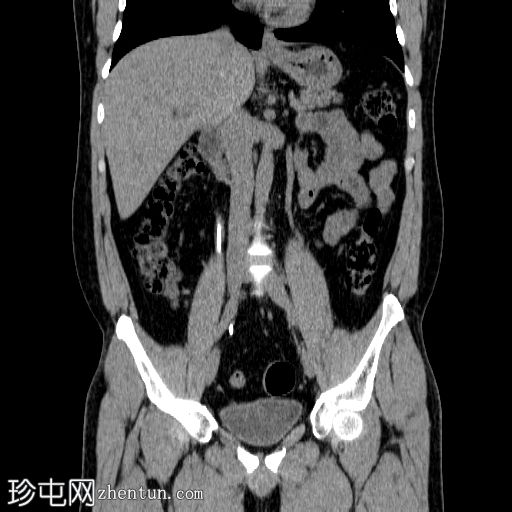

右侧输尿管支架置入。随访CT扫描。

冠状位

平扫

右侧输尿管双J管置入良好,自右肾盂延伸至膀胱。

未见肾积水或肾周积液。

未见输尿管周围脂肪条索状改变。

输尿管支架常用于缓解各种原因引起的尿路梗阻。置入可采用顺行或逆行途径。